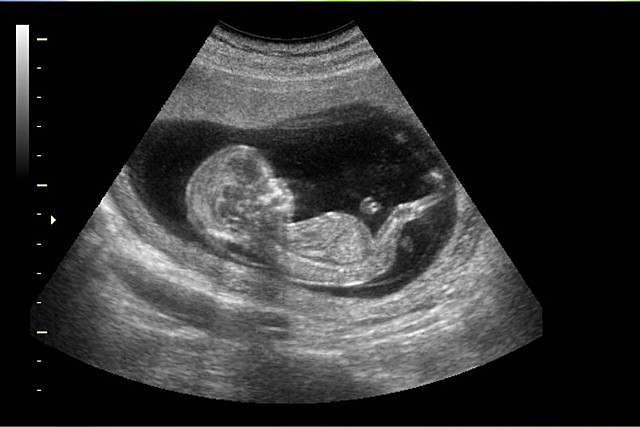

• Ecografía

Ecografía

Surge de la investigación del cardiólogo sueco Edler y el obstetra escocés Ian Donald et al. Volvió a cambiar la práctica médica y obstétrica con una técnica más segura, sin radiación, para evaluar tanto el cuerpo como el feto en el útero.